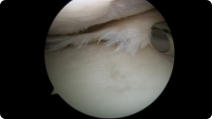

Arthroscopic image of an ACL tear Arthroscopic image of an ACL reconstruction

ACL Tear